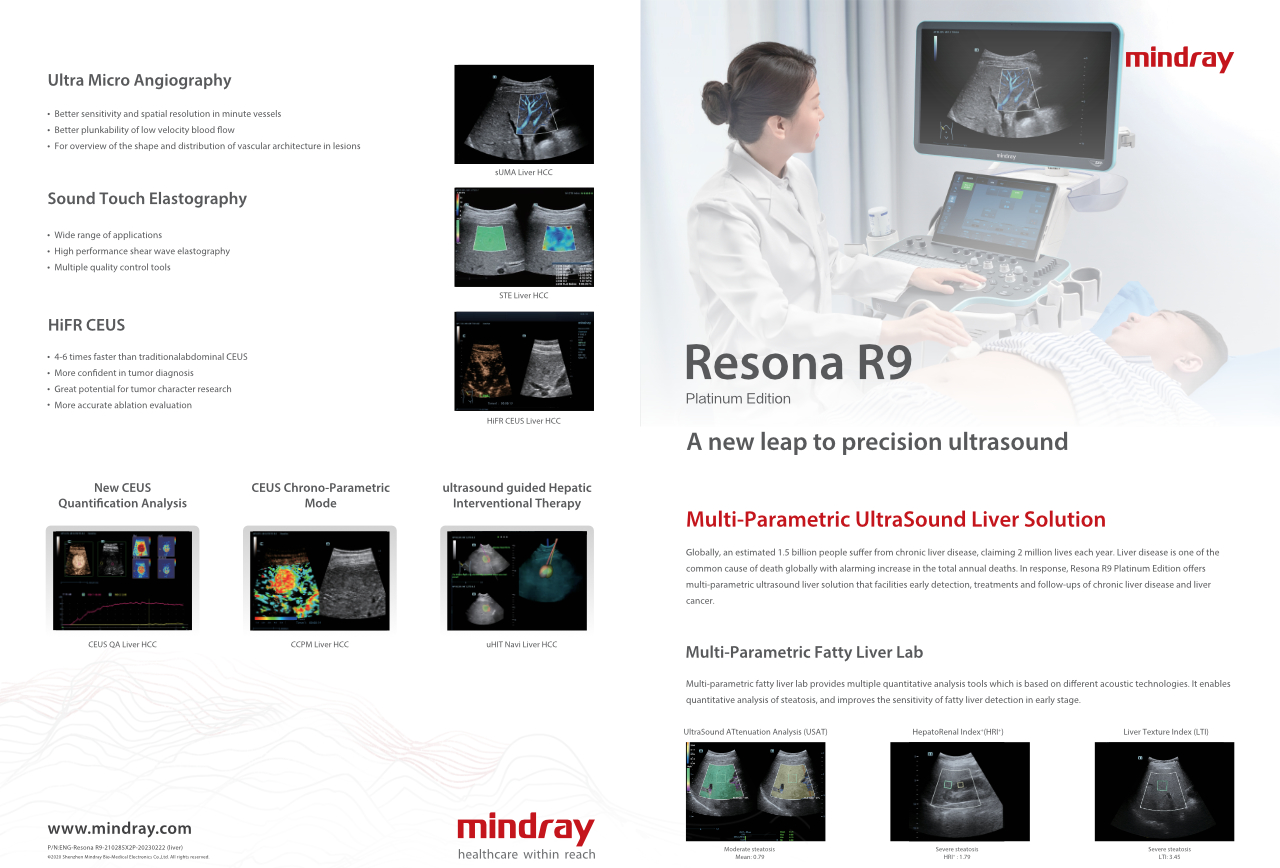

Hoe duidelijk is een lever te zien?

Bij focale leverlaesies, zoals hemangioom of leverkanker, speelt ultrasone contrastbeeldvorming een belangrijke rol. Ultrabrede niet-lineaire UWN+ contrastbeeldvormingstechnologie kan helpen bij het verkrijgen van een betere penetratie, een hogere contrast-weefselverhouding, met een lagere MI en een langere observatie van de perfusietijd.